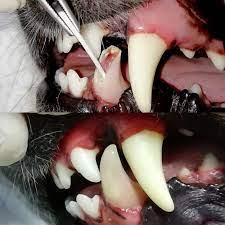

Endodoncia Animal

Estas corrigen los defectos e irregularidades de la posición de los dientes, ya que si no están bien ubicados impide un correcto funcionamiento masticatorio llegando a afectar hasta la respiración. Entre ellos Brackets y Retenedores..

Todos los animales requieren atención y cuidado.

¡Cuídalos, ellos dependen de ti y necesitan de tu protección!